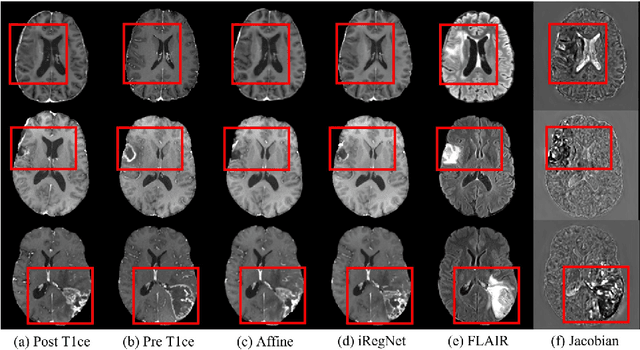

Abstract:Reliable and accurate registration of patient-specific brain magnetic resonance imaging (MRI) scans containing pathologies is challenging due to tissue appearance changes. This paper describes our contribution to the Registration of the longitudinal brain MRI task of the Brain Tumor Sequence Registration Challenge 2022 (BraTS-Reg 2022). We developed an enhanced unsupervised learning-based method that extends the iRegNet. In particular, incorporating an unsupervised learning-based paradigm as well as several minor modifications to the network pipeline, allows the enhanced iRegNet method to achieve respectable results. Experimental findings show that the enhanced self-supervised model is able to improve the initial mean median registration absolute error (MAE) from 8.20 (7.62) mm to the lowest value of 3.51 (3.50) for the training set while achieving an MAE of 2.93 (1.63) mm for the validation set. Additional qualitative validation of this study was conducted through overlaying pre-post MRI pairs before and after the de-formable registration. The proposed method scored 5th place during the testing phase of the MICCAI BraTS-Reg 2022 challenge. The docker image to reproduce our BraTS-Reg submission results will be publicly available.